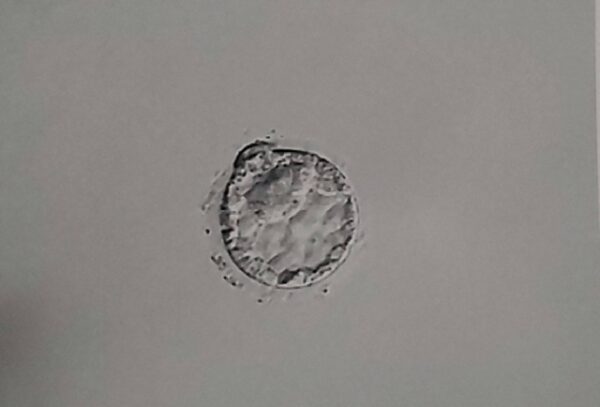

体外受精(IVF)で胚盤胞凍結をされた方が、治療をやめるに際し胚盤胞の供養をして欲しいと実際に御供養に来院されるケースが近年増えてきています。

不妊治療は「出口の見えないトンネル」とも言われ、頑張って治療と向き合って来た自身の区切りとして、そして胚盤胞であってもかけがえのない我が子への想いを込めて御供養をされる方がいらっしゃいます。